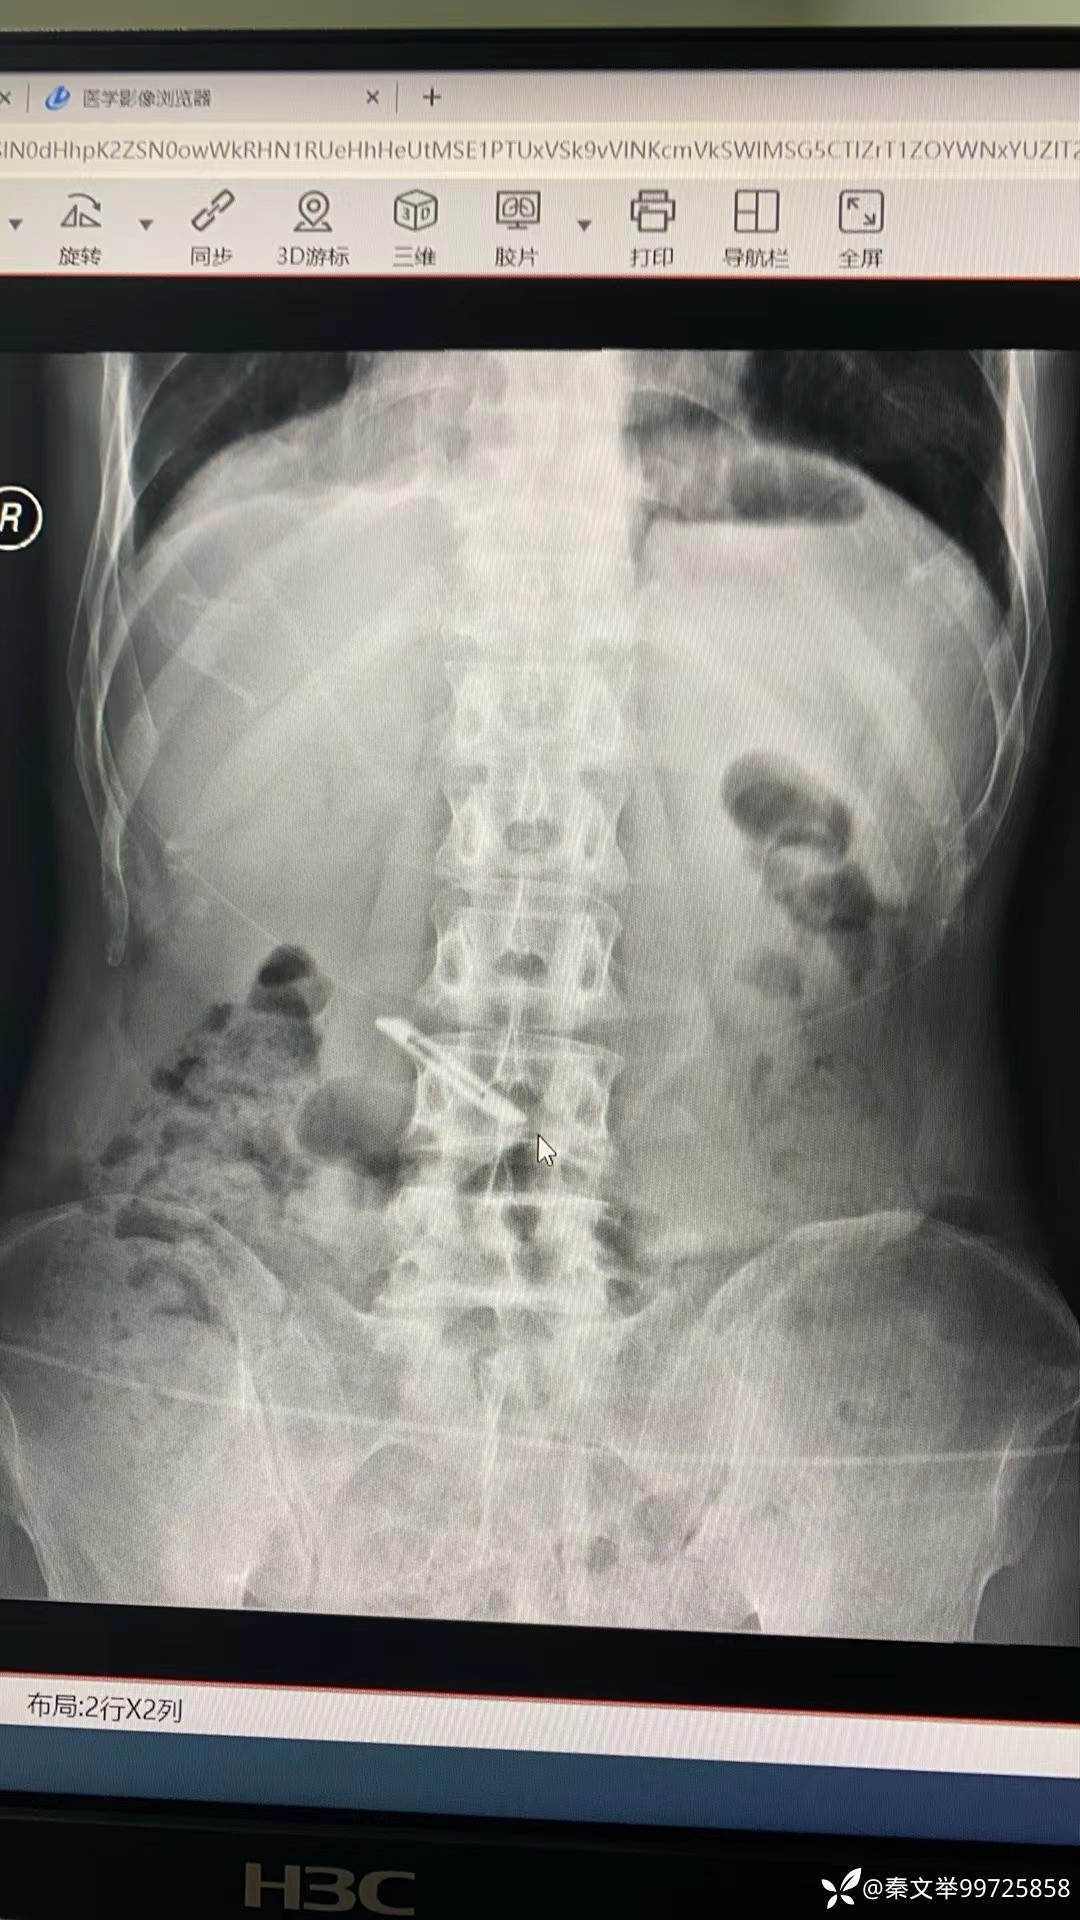

中年患者,一名嫌疑犯,被公安人员抓捕时吞下一枚手术刀片,被移送到我院要求取出刀片。

由于不清楚刀片性质,担心取出过程中损伤食管粘膜,决定做一个保护装置。